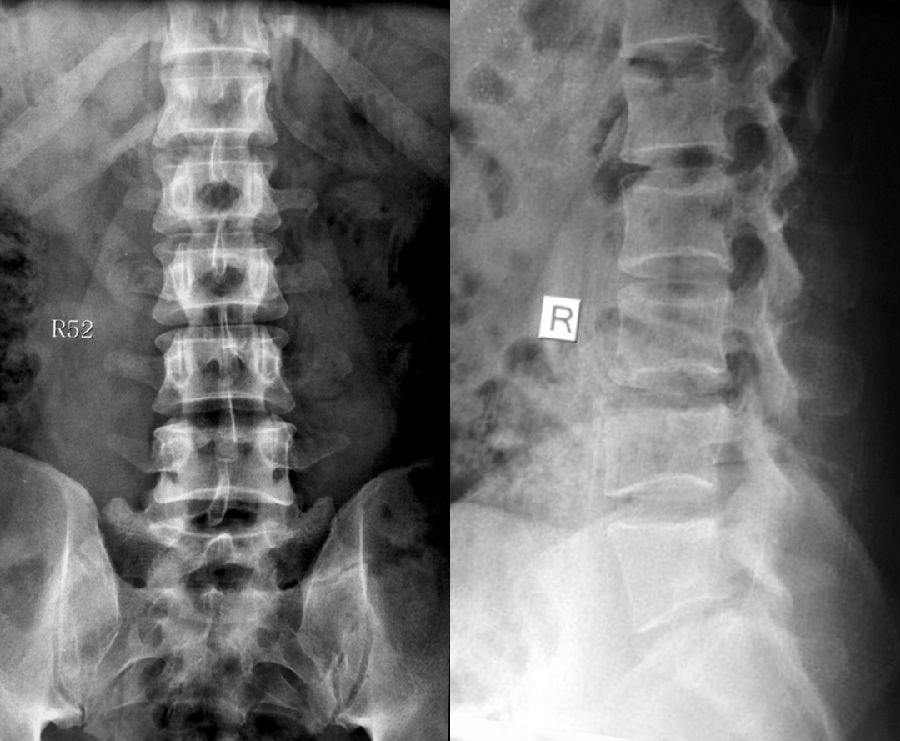

IV型:一侧为II型即腰5横突与骶骨形成假关节,对侧为III型即腰5横突与骶骨形成骨性融合

IV型即混合型:L5双侧横突肥大,一侧与骶骨相接触为Ⅱ型表现,另一侧与骶骨形成骨性融合为Ⅲ型

它与腰骶部疼痛存在密切的相关性是不可忽视的,并干扰诊断与之症状相近的其它疾病,如椎间盘突出、致密性骨炎、强直性脊柱炎等等,当然这其中有些疾病可以并存,X线、CT检查在腰骶部移行椎的诊断中有重要意义,不仅能对本病做出诊断,并且有助于鉴别诊断。